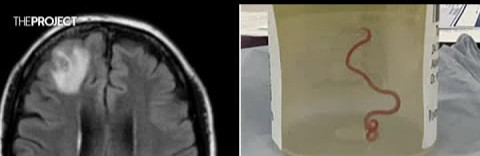

සහ දඟලනවා." ස්නායු ශල්ය වෛද්ය හරි ප්රියා බන්ඩි සිය රෝගියාගෙන් සෙන්ටිමීටර 8 ක් දිග පරපෝෂිත වට පණුවෙක් ඇදගෙන ගොස් ඇති අතර, ඊළඟට කුමක් කළ යුතුද යන්න පිළිබඳ උපදෙස් සඳහා සේනානායක සහ අනෙකුත් රෝහල් සගයන් ඇමතීමට ඇය පොළඹවා ඇත.

ඇයගේ මොළයේ MRI ස්කෑන් පරීක්ෂණයකින් ශල්යකර්මයක් අවශ්ය වන අසාමාන්යතා අනාවරණය විය.

විස්මිත සොයාගැනීම නිසා රෝහලේ කණ්ඩායමක් ඉක්මනින් එකතු වී එය කුමන ආකාරයේ වටකුරු පණුවෙක්ද යන්න අනාවරණය කර ගැනීමට සහ වඩාත් වැදගත් ලෙස රෝගියාට අවශ්ය ඕනෑම වැඩිදුර ප්රතිකාරයක් තීරණය කිරීමට පෙළඹුණි.

"ඔහු එය දෙස බලා, 'අනේ මගේ යහපත, මේ ඔෆිඩස්කාරිස් රොබට්සි' යැයි කීවේය. Ophidascaris robertsi යනු සාමාන්යයෙන් පිඹුරන් තුළ දක්නට ලැබෙන වට පණුවෙකි.

කැන්බරා රෝහලේ රෝගියෙකු මිනිසුන්ගෙන් සොයා ගන්නා පරපෝෂිතයා පිළිබඳ ලොව පළමු අවස්ථාව සනිටුහන් කරයි.